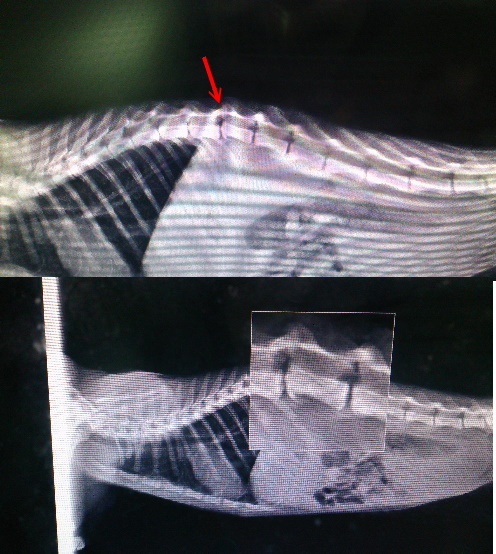

1/27(一)豐原的中泰動物醫院救醫 照X光後醫生說脊椎挫傷,並打了一隻針,開了一個禮拜的藥。

醫生看完之前X光後說明病情:右側腸骨與薦狀連合接合地方裂開 最後胸椎與第一腰椎間受傷